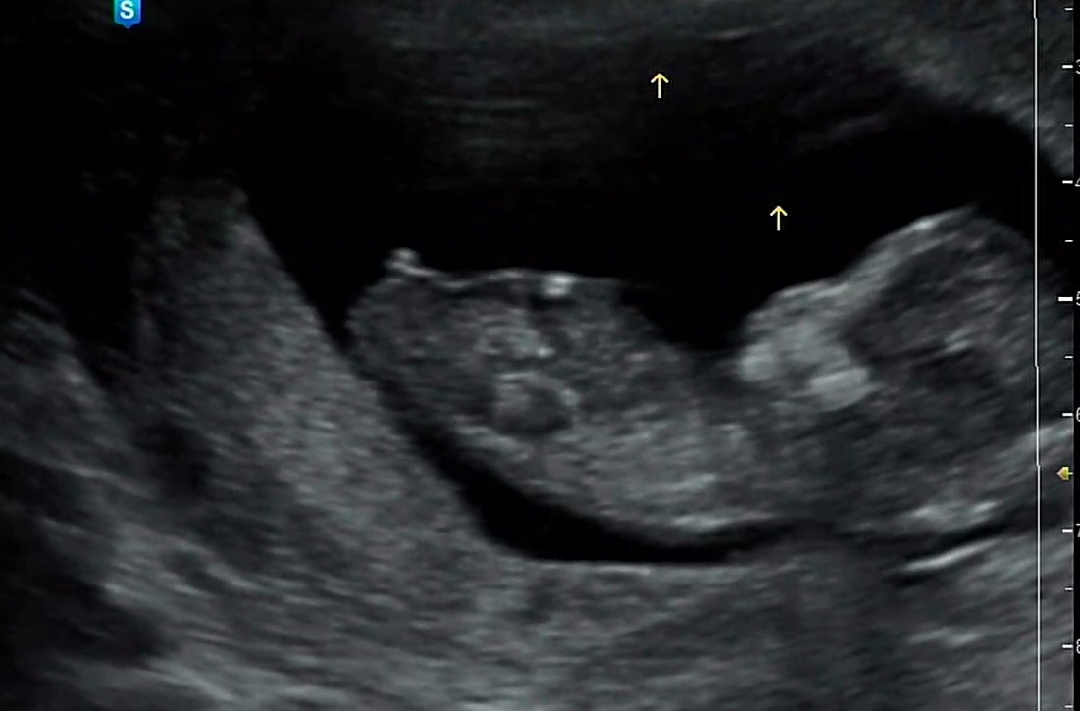

새로운 원장님이 찍어주신 초음파

의사쌤을 바꾸어보았는데 사진을 엄청 잘 찍어주셨어요! 아들일까요? 딸일까요?

애매하긴한데 아들같아요!